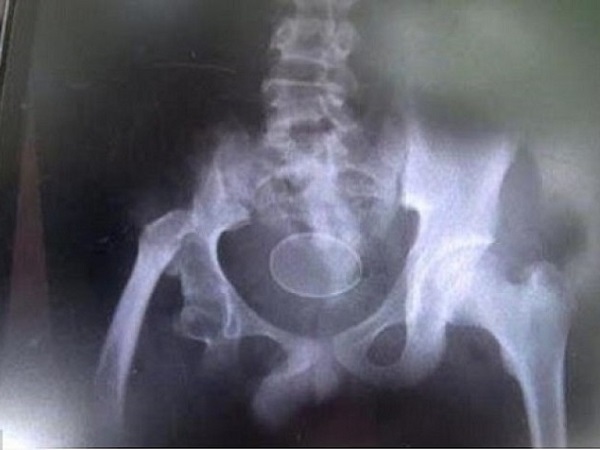

Hiện các bác sĩ đang lưu chú nhóc Akmal tại một phòng đặc biệt của bệnh viện để nghiên cứu chi tiết về tình trạng dị thường này. Theo kết quả chụp chiếu mới nhất thì trong cơ thể của Akmal cũng đang có sẵn một quả trứng chờ… đẻ!